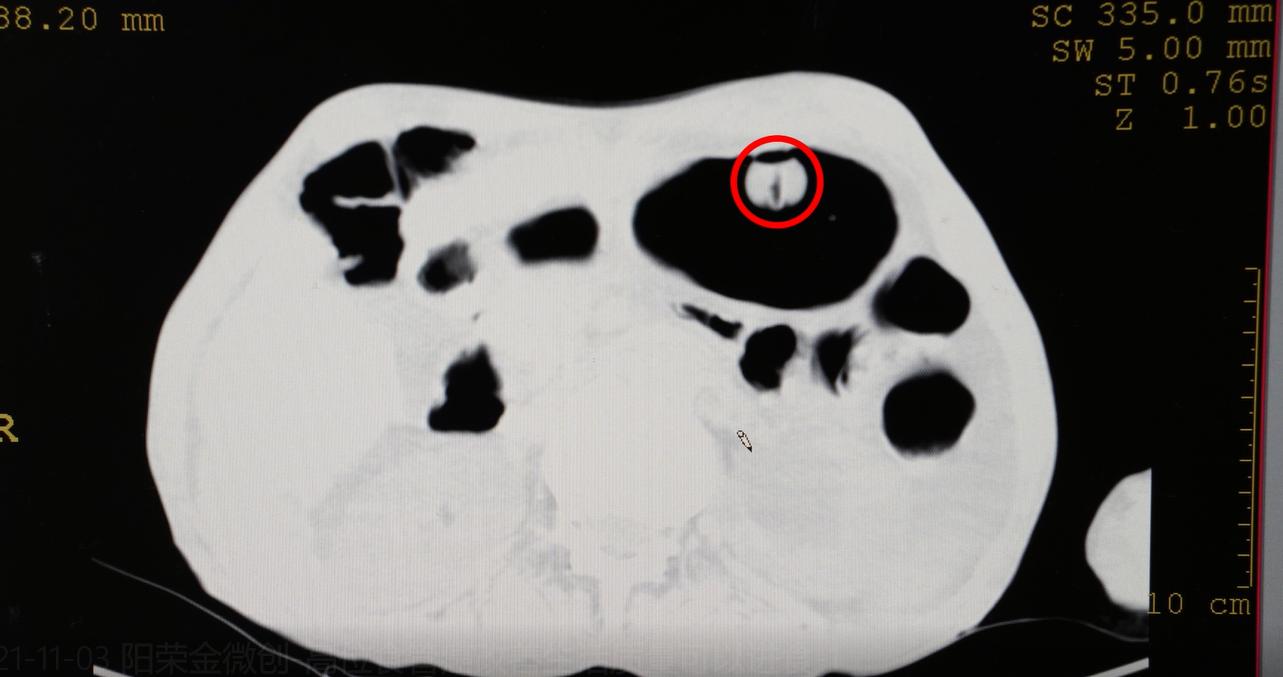

70岁高位食管癌患者,之前做过放疗,之后形成了食管气管瘘,脖子食管处已经瘘得比较严重。很长时间没有吃东西靠输液维持营养,来的时候已经骨瘦如柴,精神状态也不太好。这个患者,考虑过给他放食管支架,但因为他的这个位置非常不好放,另外还有放了支架以后会出现几个问题:

开始时给他放了一个胃肠管,但时间长了会引起肺部感染。所以,还是需要解决这些问题,经过MDT会诊,并与家属充分沟通,决定给患者做胃造瘘。

胃造瘘就是从胃的表皮打一个孔,放一根管子进去,这个手术不算复杂,也是微创的,不到一小时就能完成。